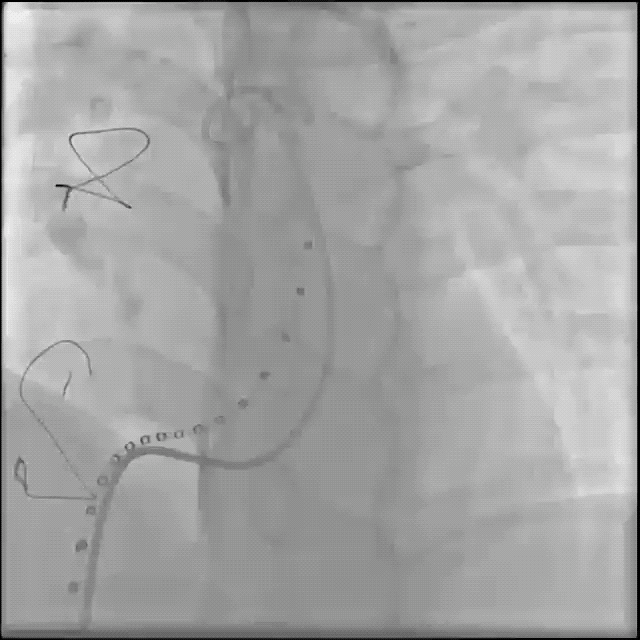

术中肺动脉造影:

重度肺动脉瓣关闭不全,大量返流。

术中球囊压迫试验:

送入超硬导丝建立轨道,送入顺应性球囊,球囊膨胀的同时行左冠状动脉造影,可见冠脉血流通畅,球囊未压迫冠状动脉。